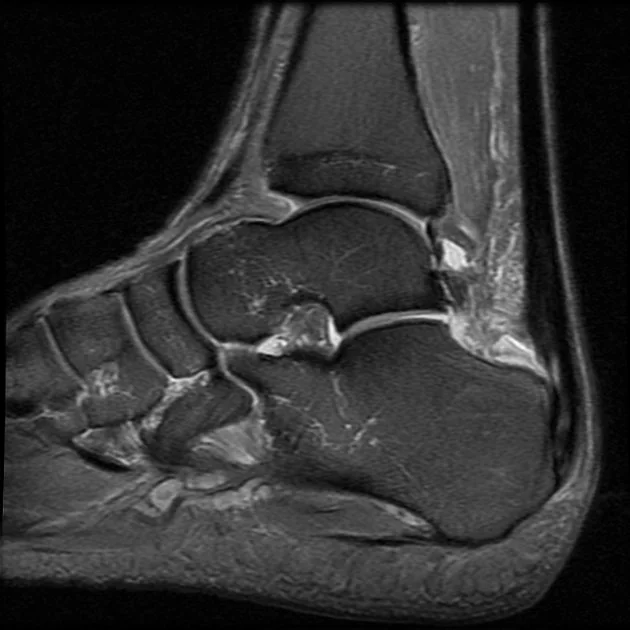

Ultrasound or MRI when needed to assess tendon degeneration

Insertional Achilles tendinopathy

Occurs where the tendon attaches to the heel bone

Often associated with bony irritation at the heel

Haglund’s deformity

A bony prominence at the back of the heel

Can worsen insertional Achilles pain